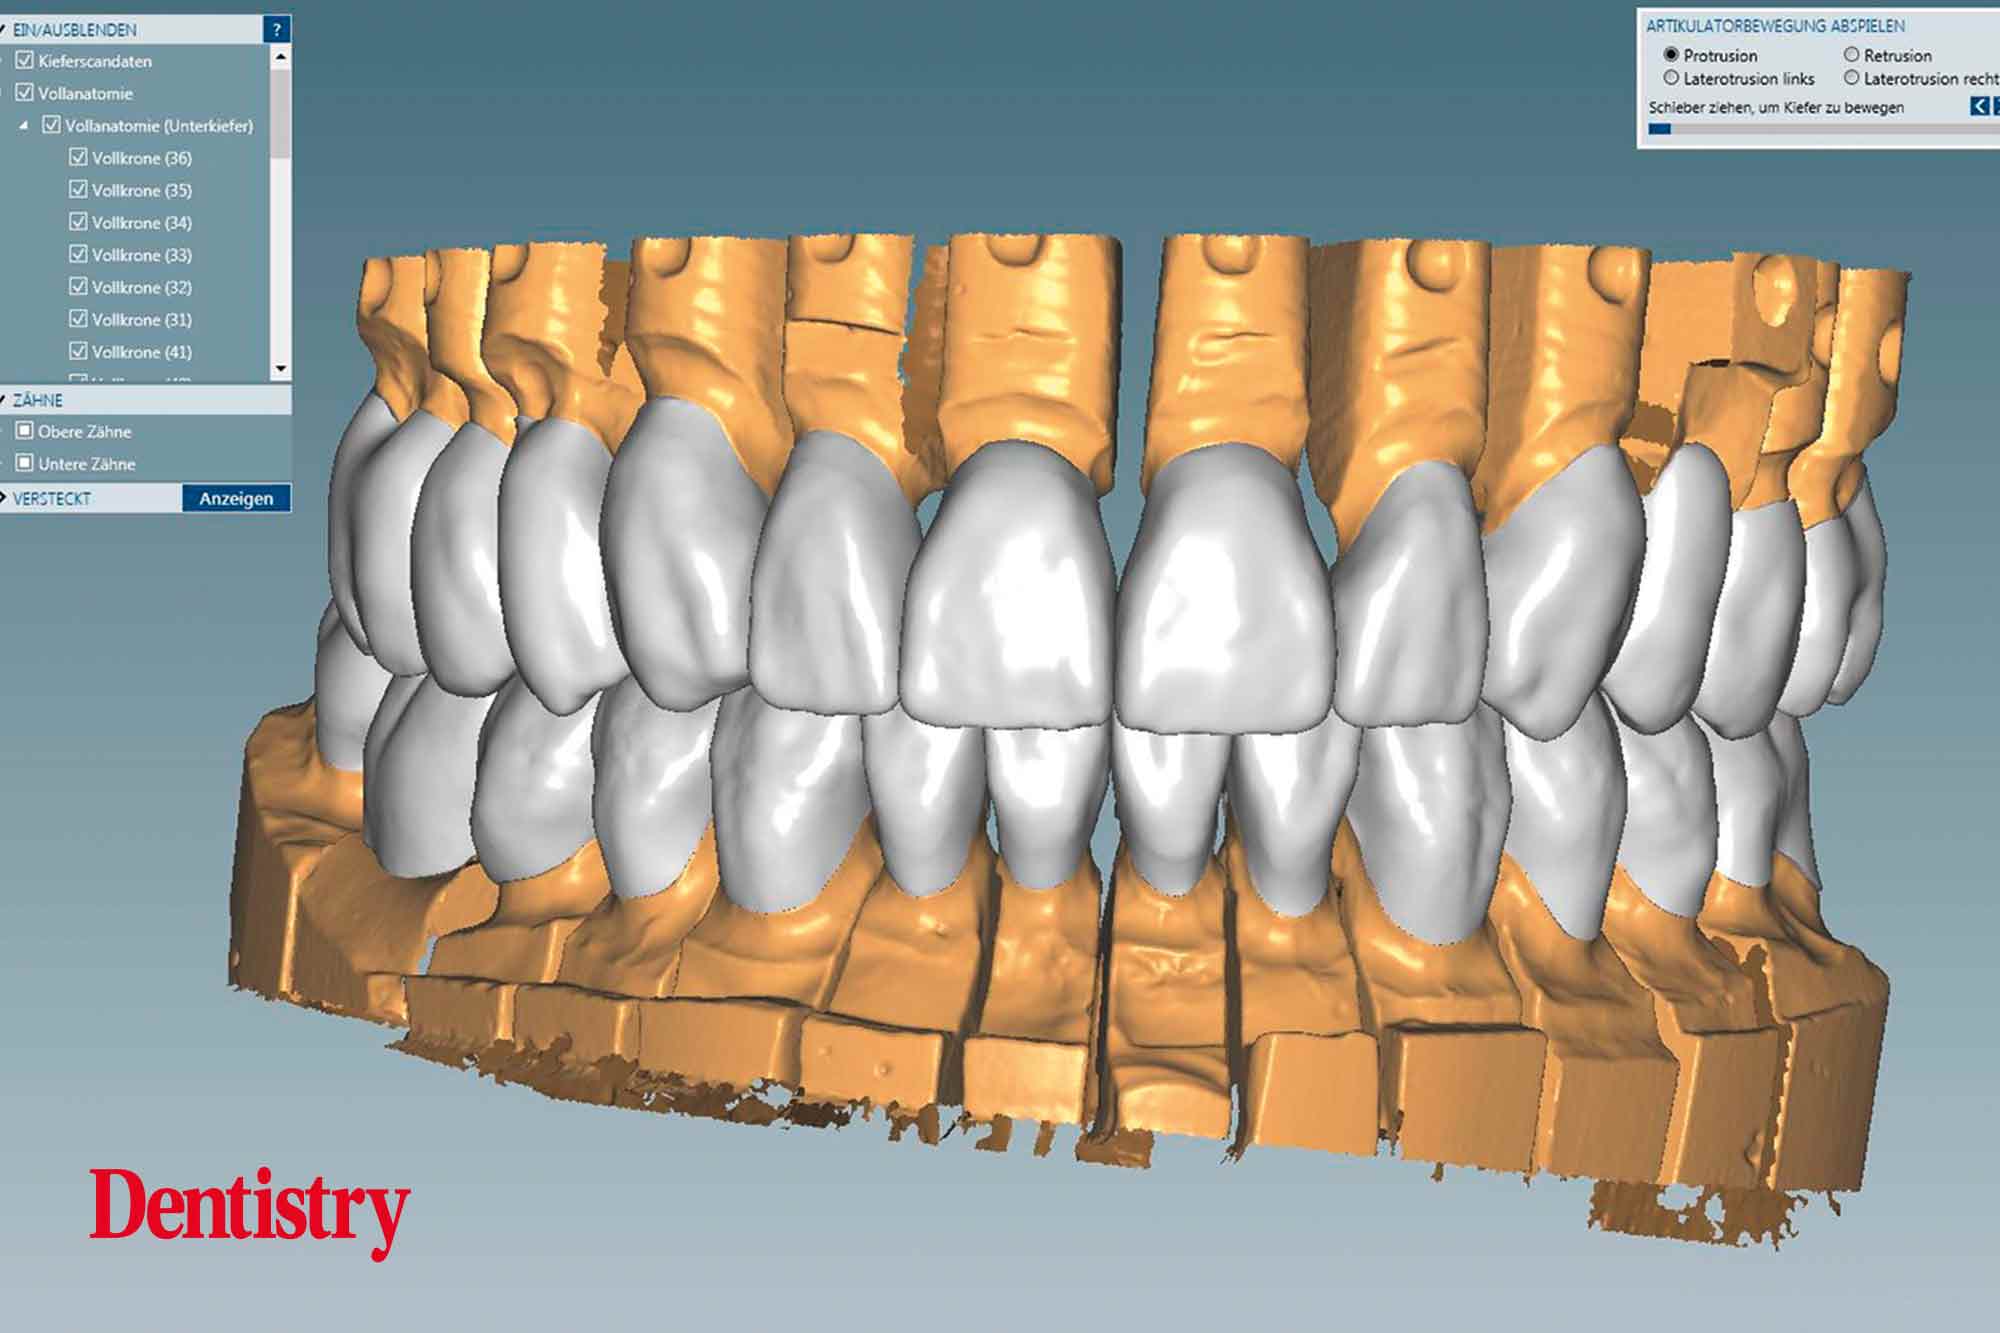

The scanned models were evaluated on a virtual 11 articulator. Temporary Ceramill PMMA (Amann Girrbach) transparent acrylic crowns were CAD planned (Figures 3a to 3d).

All patient parameters including condylar inclination were transferred to the Ceramill Artex articulator and the lateral and protrusive excursions were established while having no contact with the anterior teeth (Figures 5 to 8).

The virtual temporary crowns were 3D printed and then temporarily cemented. This test phase with temporary crowns is a mandatory step because after the patient evaluated the temporary crowns for several weeks, corrections were made with the input of the patient, thus reducing the risk of errors in the subsequent final crowns.